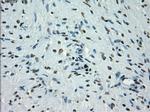

PRKY Monoclonal Antibody (OTI3E10), TrueMAB™

A group of proteins that are intimately involved in this process are the serine/ threonine (Ser/Thr) protein kinases. PRKY (protein kinase, Y-linked) and PRKX (protein kinase, X-linked) are members of the Ser/Thr protein kinase family, both of which belong to the subfamily of cAMP-dependent kinases. Encoded by a gene that is located near the pseudoautosomal region on chromosome Y, PRKY contains one protein kinase domain through which it catalyzes the ATP-dependent phosphorylation of target proteins. Functioning in a similar manner to PRXY, PRKX contains one protein kinase domain and is essential for macrophage differentiation and renal epithelial cell migration. Defects in the genes encoding PRKY and PRXX are associated with sex reversal disorder, namely XX in males and XY in females.